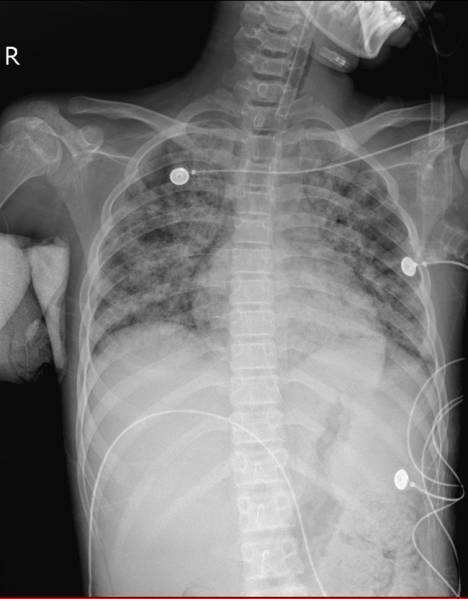

治疗前患儿胸片

确定治疗方向后,由于病情急剧进展,患儿于入院第三天转入ICU治疗。在呼吸机给予100%纯氧的情况下,患儿病情依然危重,床旁胸片显示患儿肺部感染十分严重。联合院内体外循环,儿科,胸外,心外科多科室专家,ICU刘主任与各位专家认为患儿具备ECMO指征。运用经皮穿刺技术为患儿应用“人工肺”,机器运转后,患儿的血氧饱和度迅速上升至97%,效果显著。